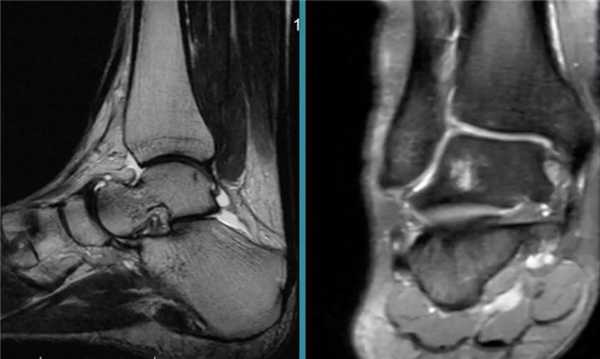

- высокоинформативные визуализирующие методы (УЗИ, МРТ) — ниже артрит на МРТ;

Артрит голеностопа на МРТ.

Для определения стадии заболевания используют визуализирующие инструментальные методы. При острых и начальных стадиях хронических артритов информативны только УЗИ и МРТ. С их помощью можно обнаружить практически любые изменения в суставах и околосуставных тканях. На поздних стадиях, когда происходит массивное разрушение костей, достаточно информативна и рентгенография. Она позволяет обнаружить характерные для артроза изменения: сужение суставной щели, остеофиты, субхондральный остеонекроз, признаки остеопороза и т.д. При остром артрите рентгенография может выявить неравномерное сужение суставной щели, которое косвенно указывает на скопление гноя.